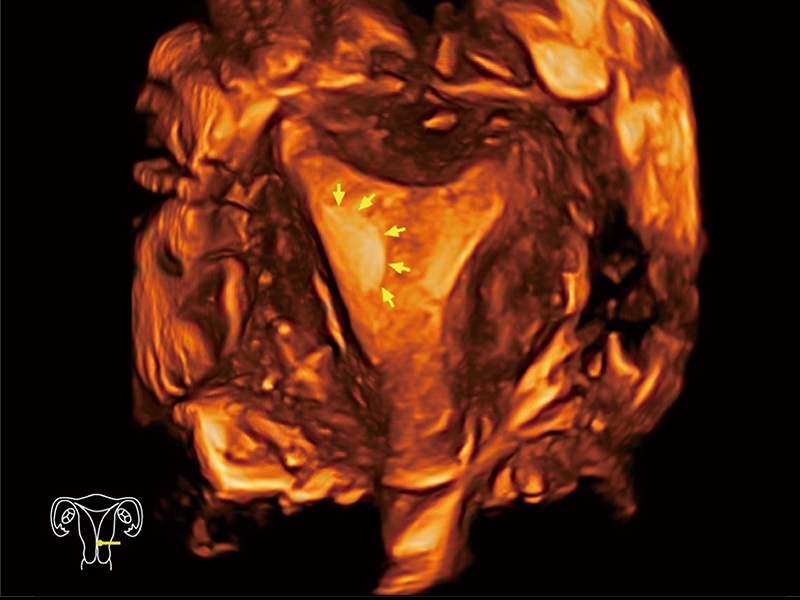

“生育问题”即关系民族复兴,也关系亿万家庭的幸福。随着婚育年龄推迟、社会压力增加等因素,越来越多人群也面临着“生不出、生不好”的问题。辅助生殖作为治疗不孕不育最有效的方法之一,也逐渐成为育儿新希望。而超声检查能为生殖需求人群的初诊评估提供宝贵的信息。 P20 Elite是哈哈体育官网匠心打造的一款生殖应用型彩超。她继承哈哈体育官网高端极光平台,突破性地将多款新型芯片及硬件模块进行整合,均衡了高端系统性能与小巧灵动机身。P20 Elite卓越的图像质量搭载专科探头,旨在为您提供全面的辅助生殖解决方案。

P20 Elite配备了丰富的生殖探头群和临床应用功能,在卵泡监测、穿刺取卵、胚胎移植、妊娠确认等领域,为生殖需求人群提供了新的临床机会,重新定义高端超声如何应用于生殖健康检查。